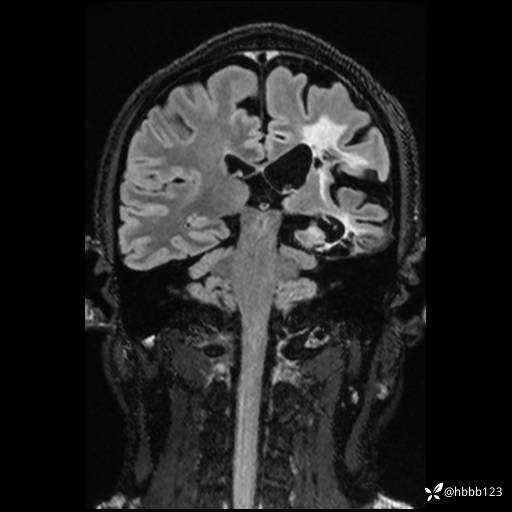

CUBE FLAIR冠状位: